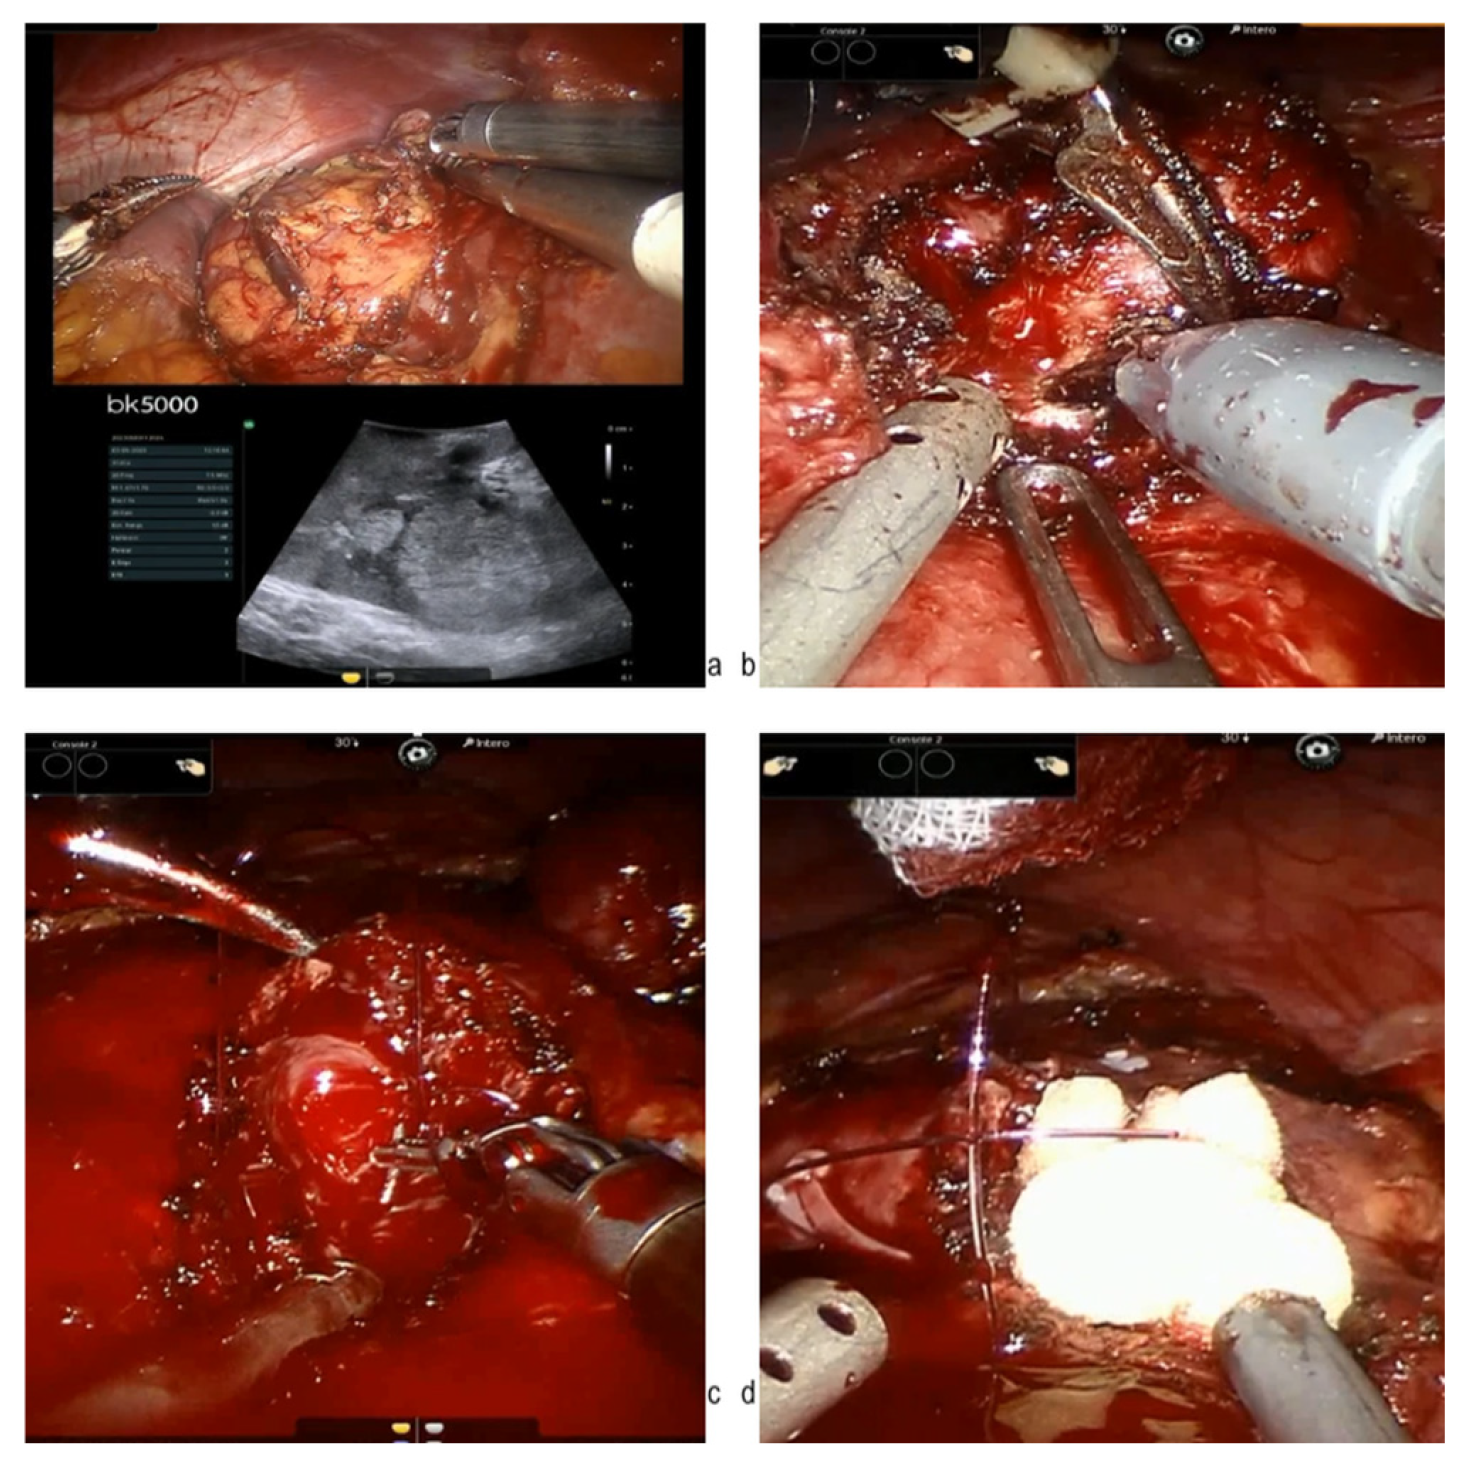

- Tuderti, G.; Brassetti, A.; Mastroianni, R.; Misuraca, L.; Bove, A.; Anceschi, U.; Ferriero, M.; Guaglianone, S.; Gallucci, M.; Simone, G. Expanding the limits of nephron-sparing surgery: Surgical technique and mid-term outcomes of purely off-clamp robotic partial nephrectomy for totally endophytic renal tumors. Int. J. Urol. Off. J. Jpn. Urol. Assoc. 2022, 29, 282–288. [Google Scholar] [CrossRef]

- Carbonara, U.; Simone, G.; Minervini, A.; Sundaram, C.P.; Larcher, A.; Lee, J.; Checcucci, E.; Fiori, C.; Patel, D.; Meagher, M.; et al. Outcomes of robot-assisted partial nephrectomy for completely endophytic renal tumors: A multicenter analysis. Eur. J. Surg. Oncol. J. Eur. Soc. Surg. Oncol. Br. Assoc. Surg. Oncol. 2021, 47, 1179–1186. [Google Scholar] [CrossRef]